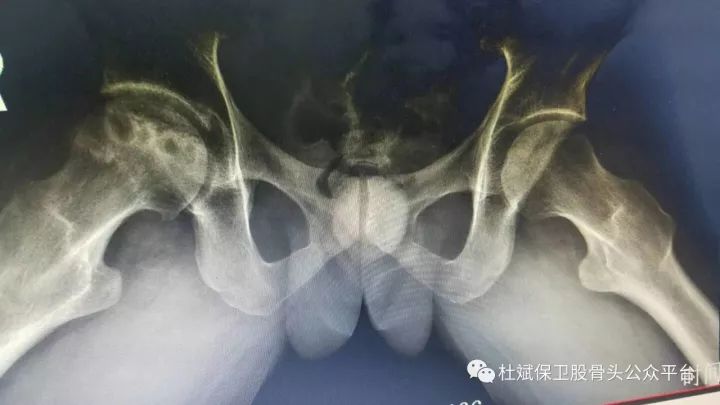

股骨头坏死怎么办 如何保髋治疗 广中医附一院方斌 股骨头 广中医附一院 方斌 内生软骨瘤 膝骨关节炎 骨巨细胞瘤 脂肪肉瘤 健康界